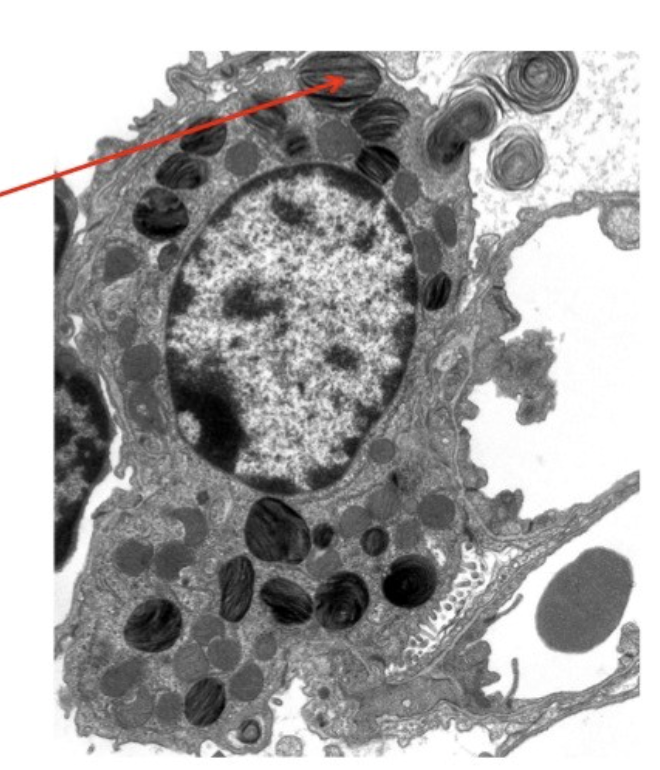

In the attached EM, the cell indicated by the arrow is most likely which of the following?

Basal cell

In the attached EM of the blood-air barrier, the structure indicated by the arrow is most likely which of the following?

endothelial cell

In the attached EM of an alveolus, the structure indicated by the arrow is most likely which of the following?

Lamellar body